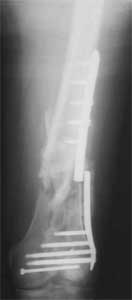

A. Difficult reductions, even in retrograde nailing (my preference, easier control of "small" distal fragment) and it is much, much harder to do it anterograde (Alex, do you have one good case in your collection of anterograde nailing in very distal fractures - as you have suggested that I

should have done it in my previously posted case?

Malpositioning is much too common (recurvatum, varus - valgus).

B. Fixation loosening: distal cutting of the nail, non-unions do happen (cases attached).

Locking Plating has more distal screws than any nail, fixed angles and provides much better fixation, especially in osteoporotic bone.